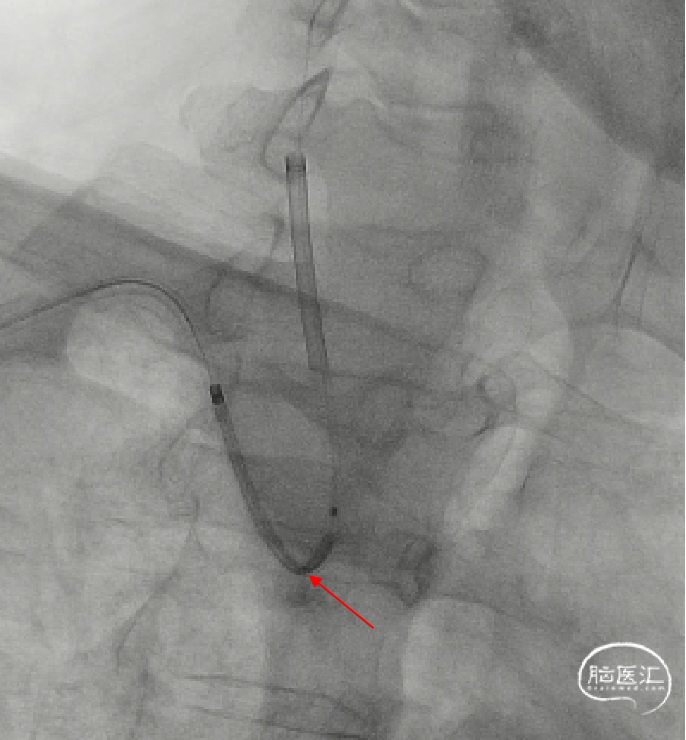

以上两种原因导致推送杆内芯被掀起,伞导丝和支架金属内芯相互抱死,无法进一步撤出支架推送系统,后来使用扭控器锁紧导丝,再用力后撤时,出现了伞导丝打折成“Z”型,支架推送系统无法再撤出了。

15、支架推送杆头端交换长度为28cm。

16、保护伞导丝“Z”型打折。